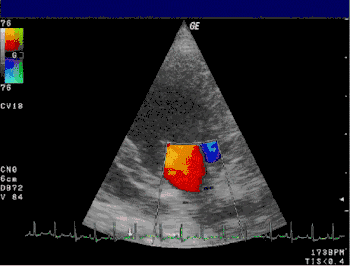

De gouden standaard voor de diagnose en de ernst van de mitralisinsufficiëntie is het afnemen van een echocardiogram. Verder kan een thoraxfoto bijdragend zijn. De aan- of afwezigheid van longoedeem kan middels een thoraxfoto worden beoordeeld en een vergroot linkeratrium kan leiden tot een zichtbaar stompe carinahoek van meer dan 60 graden.